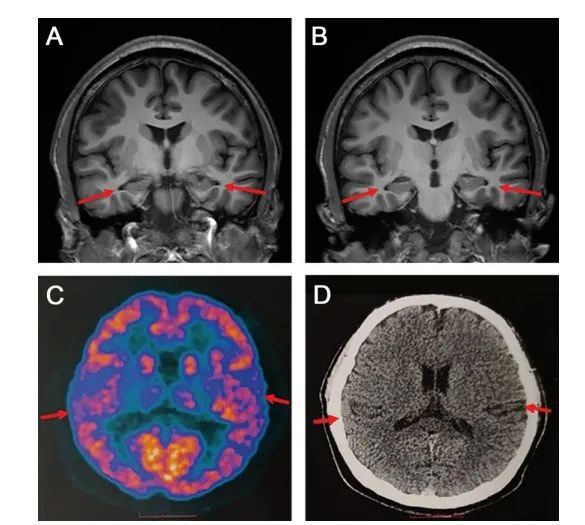

根据研究小组提供的资料显示,该患者在就诊前两年开始出现在学习时注意力难以集中,一年后,短期记忆丧失明显,无法回想起前一天发生的事或个人物品的存放位置,阅读困难,反应缓慢。

随着病程进展,记忆力进一步下降,经常丢失个人物品,记不清自己是否吃过饭,难以完成学习内容和老师布置的作业。由于记忆下降严重,他的学习成绩从之前的中等以上水平下滑到班内末位,无法完成学业,不得不从高中退学。

宣武医院神经内科主任医师、博士生导师贾龙飞表示,该病例的发病年龄十分罕见,开始时他也曾有点不相信检查的结果,因为此前虽然确实发现过20多岁罹患阿尔茨海默症的患者,但这类患者往往会存在基因突变或家族史。

“但最终经过全面的检查,我们确认这次的患者没有家族史,以现有的手段也无法查到基因突变。这种情况确实极为罕见。”